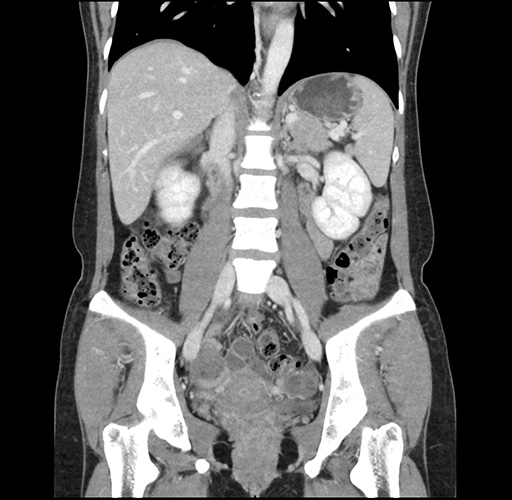

Imaging Analysis

Look through the patient's CT scan to identify any areas of concern for the necessary procedure.

Based on your CT findings, which issue(s) would give reason for "planned slowing down moment(s)" in this case?

Considering a standard left lateral sectionectomy procedure, what step(s) of the operation would you do differently in this case ?